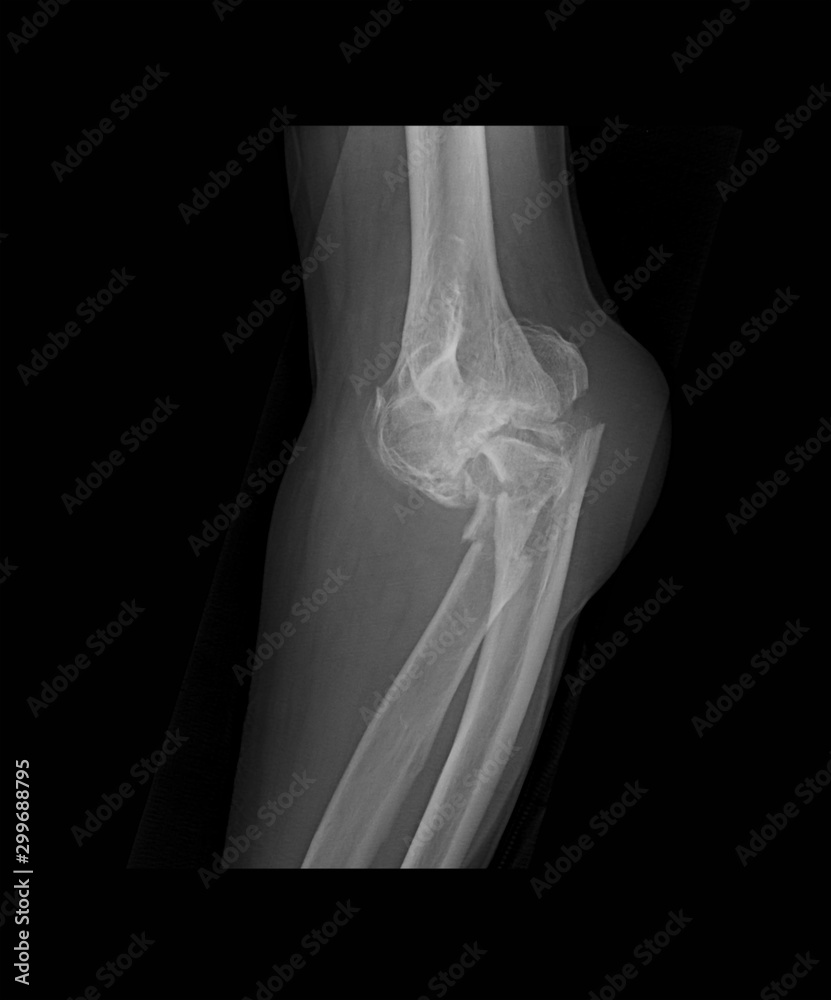

Left elbow Xray (left panel lateral view, right panel... Download from www.researchgate.net

Left elbow Xray (left panel lateral view, right panel... Download